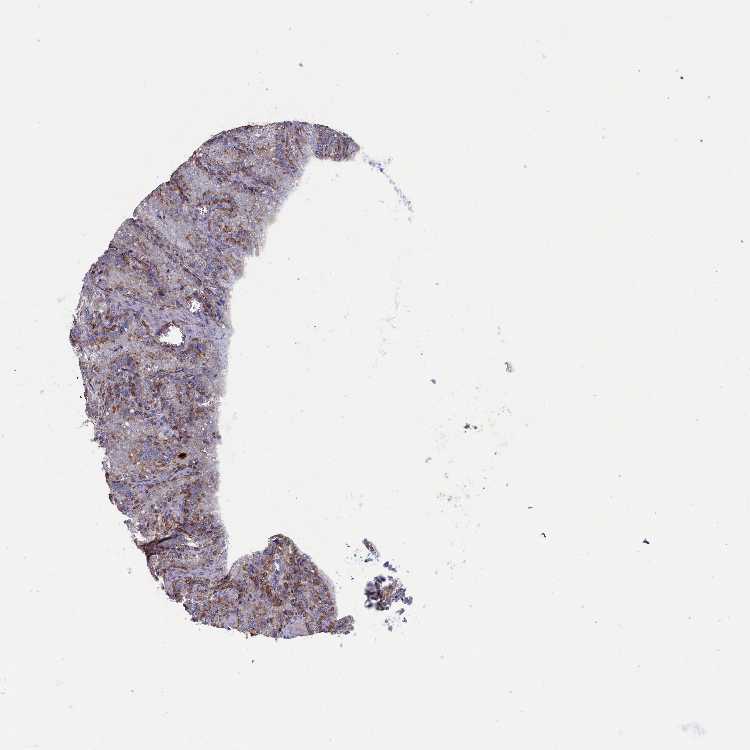

SEMINAL VESICLE - Antibody stainingi

Antibody staining in the annotated cell types in the current human tissue is reported as not detected, low, medium, or high, based on conventional immunohistochemistry profiling in selected tissues. This score is based on the combination of the staining intensity and fraction of stained cells.

Each image is clickable and will lead to virtual microscopy that enables deeper exploration of all samples and also displays staining intensity scores, fraction scores and subcellular localization as well as patient and tissue information for each sample.

Antibody HPA043212

Glandular cells High